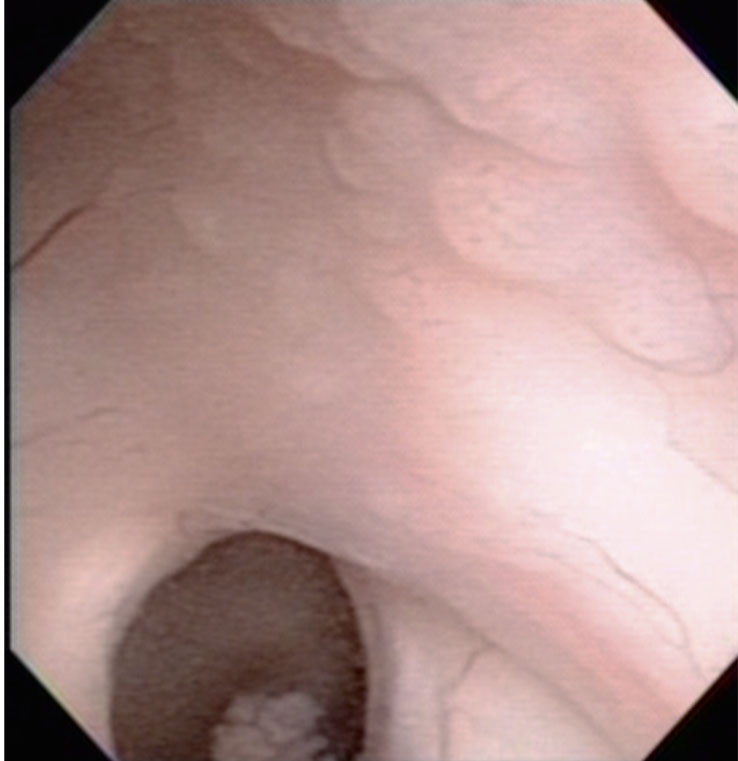

Peroperative view during endoscopic surgery in a boy with neurohypophyseal and pineal germinoma. There are numerous tiny nodules on the wall of right lateral ventricle.

These lesions are neither tumor CSF seeding nor dissemination. Germinoma cells always invades into subependymal glial tissue and spread to the whole ventricular system including the ovex. This has been called as subependymal infiltration (extension) of germinoma. Third ventriculostomy at the tuber cinereum in front of the mammillary bodies and tumor biopsy at the pineal lesion were shown.